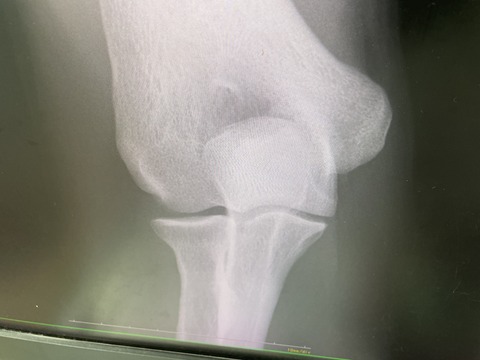

本日も、朝から夜まで、一般患者様を

見さしてもらいながら

トップアスリートが4人来ました

茨城トヨペット社会人野球、151キロを投げる

プロからスカウトをもらってる、ピッチャー、

IMG_8592

硬式社会人野球 147のキロを投げる、

元甲子園全国制覇をした、履正社高校の

エースピッチャー

IMG_8602

全日本高校空手道選手権優勝の  女子空手選手

IMG_8603

全日本モトクロス選手権、5回連続全日本

チャンピオンの

選手たちも来院されました!

IMG_8595

かなりハードでしたが、やりがいのある1日でした!